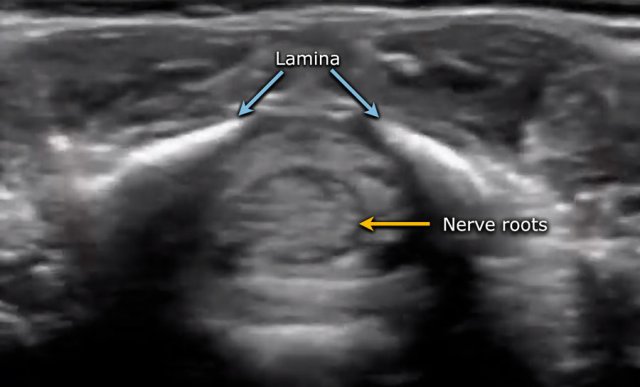

The spinal cord is depicted as a very hypoechoic structure with a central echogenicity.

This central echogenicity is supposed to represent the interface between the anterior commissure and the median anterior fissure, and not the central canal.

Axial image of the spinal cord with central echogenicity.

Axial image of the cauda equina.

The lower end of the cord is thickened, which is the lumbar intumescence.

The cord tapers in a sharp cone (blue arrow).

The cauda equina is seen as a bunch of moving strands.

If the baby is lying in the decubitus position, the strands will gravitate to the dependent posterior side.

If the baby is examined in the prone position with a pillow under the abdomen, the stands will move ventrally.

Always obtain axial views.

The movement of the nerve roots is better seen in the transverse plane compared to the sagittal plane and it is easier to assess intraspinal pathology like a thickened filum.